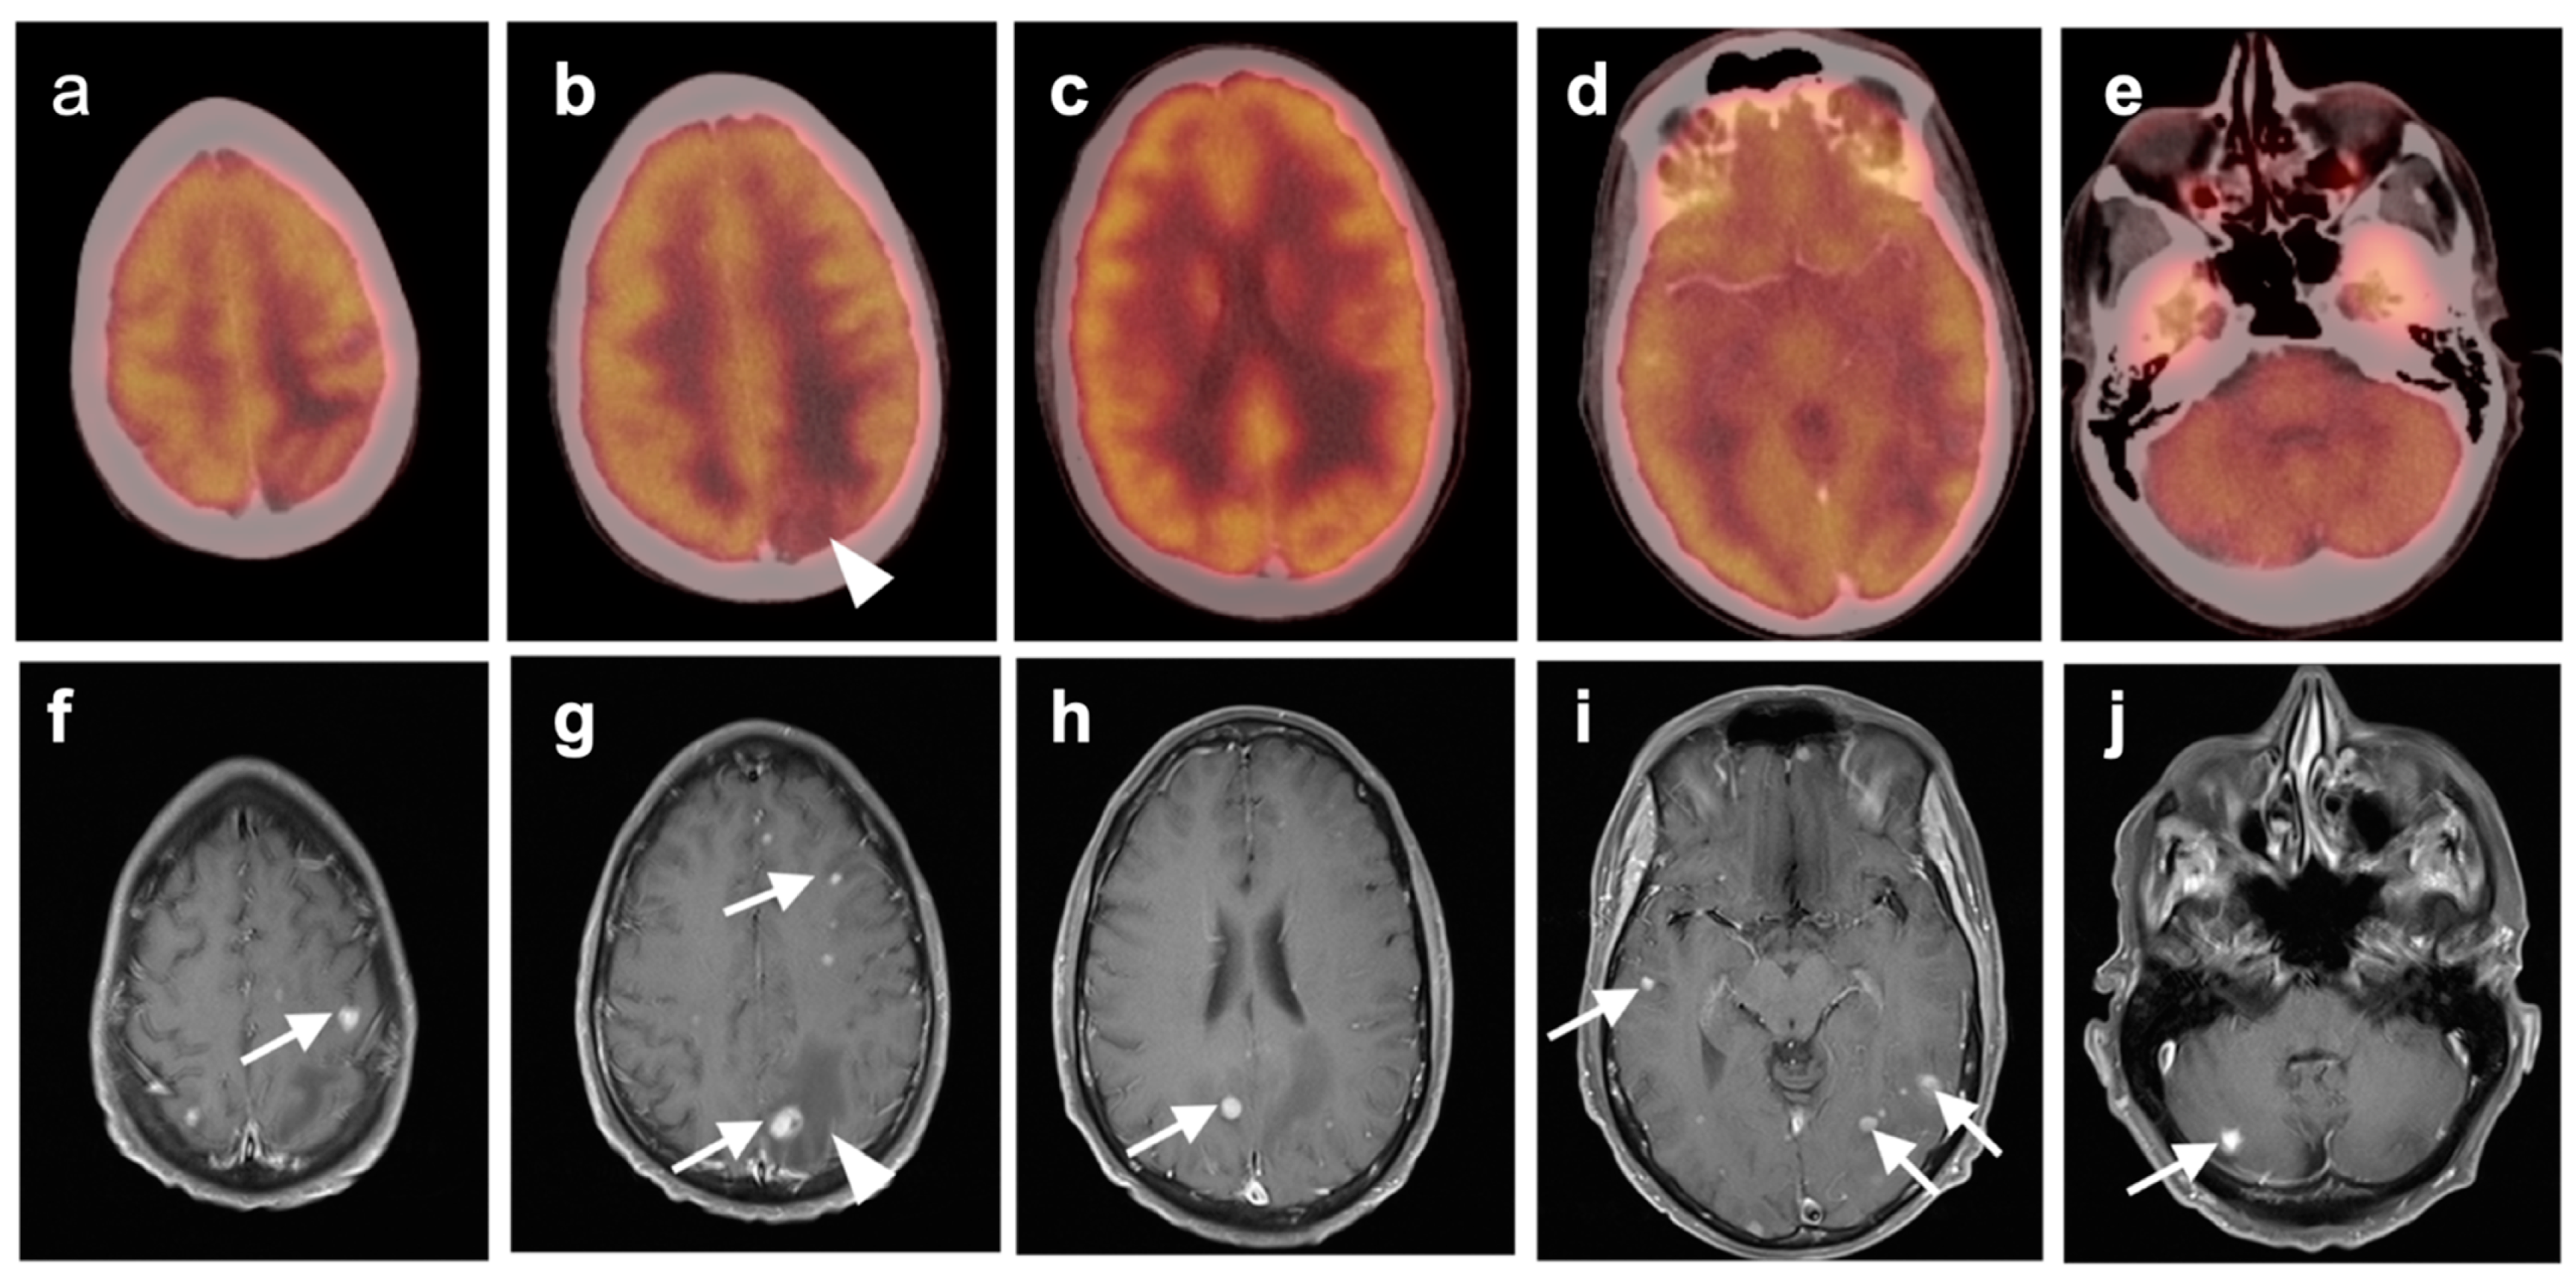

3.5. Brain Metastases

3.6. Response to Therapy

3.7. Meningioma